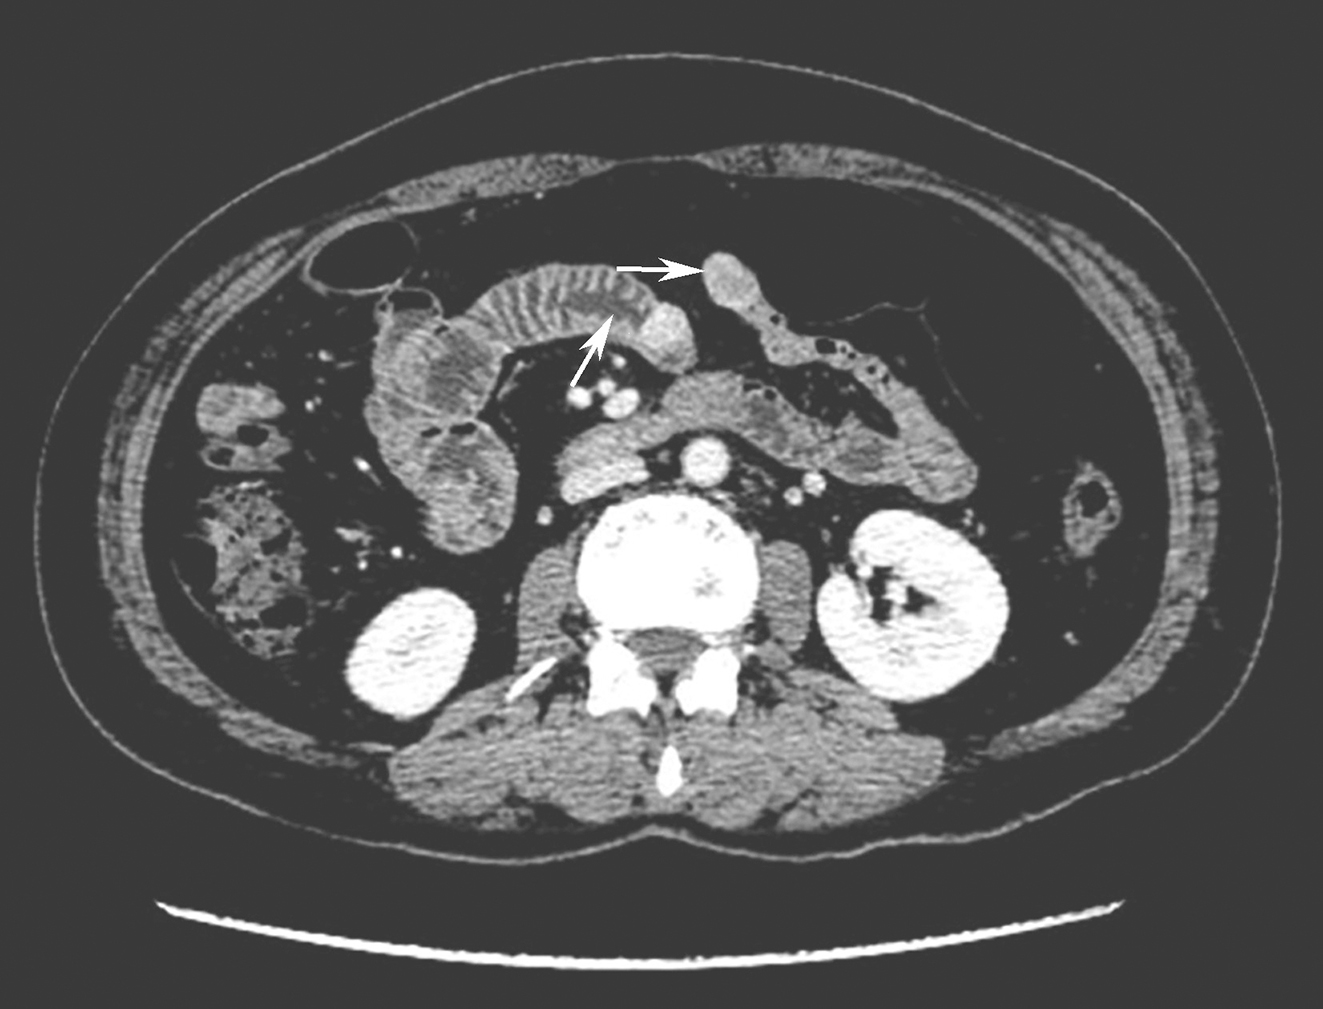

全腹部增强CT:①胆囊多发结石,胆囊炎;②小肠多发结节,富血供,需考虑胃肠间质瘤、神经鞘瘤或血管球瘤等可能;③降主动脉旁结节,考虑神经源性肿瘤;④双下腹壁皮下结节,请结合临床(图1)。

图1腹部CT提示小肠多发富血供结节

引自:胃肠间质瘤典型病例诊治与解析.第1版.ISBN:978-7-117-30146-6.主编:陶凯雄 曹 晖